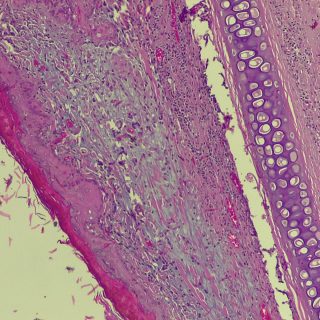

A vírus a csípést követően a bőrben elszaporodik, majd bekerül a véráramba, és a belső szervekben egy ismételt szaporodás után végül újra a bőrbe jut. Itt kialakulnak a klasszikus elváltozások, amelyek lényegében göbképződéssel járó gyulladásnak felelnek meg. A kórokozó hatására az irharétegben kialakulnak az ún. myxomasejtek (a myxomasejtek a mesenchyma-sejtekből kialakuló, nagy, sokszor nyúlványokkal rendelkező, módosult sejtek, amelyek tipikusak a myxomatosisban elhullott állatok irha rétegében) is. Az eddigi megfigyeléseink szerint a göbök a legintenzívebben a szemhéjakon, a száj körüli bőrképletekben és a genitáliákban jelennek meg, amelyet súlyosfokú vizenyő is kísér. Szövődményként gennyes jellegű orrgyulladás, bakokban tasakgyulladás és ivartól függetlenül kötőhártya-gyulladás is fellép, ami az érintett egyedek tájékozódási zavarával is jár. Mindennek eredményeként az állat lényegében képtelenné válik az életben maradásra: táplálkozása akadályozott, könnyű prédává válik a ragadozók számára és közútra tévedve gyakran a forgalom áldozatává válik.